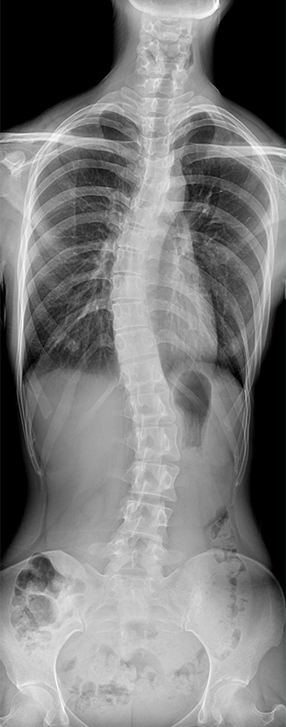

• 标配全身拼接功能

无缝融合处理,保证高质量全景影像。